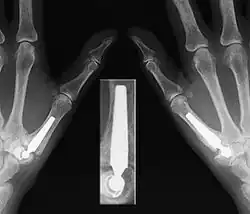

Gesichert wird die Diagnose durch eine Röntgenaufnahme. Jedoch gibt das radiologische Ausmaß einer Sattelgelenkarthrose keine Auskunft über die Schmerzintensität, die ein Patient empfindet. Es gibt Patienten mit fortgeschrittenen Krankheitszeichen in Röntgenbildern, die keine wesentlichen Schmerzen verspüren und umgekehrt.

Aufgrund der neuen Entwicklung liegen erst für die wenigsten Prothesen Überlebensraten für die ersten fünf Jahre vor. Für die Arpe-Prothese zeigen zwei Studien eine Überlebensrate von 85 % bzw. 97 % nach fünf Jahren. Für die Elektra-Prothese zeigt eine Studie eine Revisionsrate von 44 % nach sechs Jahren. Das Hauptproblem ist weiterhin eine aseptische Prothesenlockerung besonders der Gelenkpfanne (wie im Röntgenbild am linken Daumen), die deutlich häufiger auftritt, je länger die Operation her ist.[6]